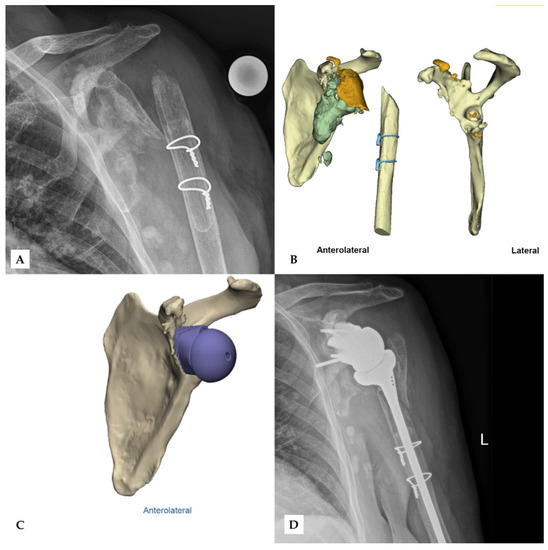

Finally, no complications were observed during surgery or in follow-up. Figure 4 and Figure 5 show two patients who received revision rTSA. The patients are very happy with the outcome. Considering the devastating initial situation, the comparison between preoperative X-rays and postoperative X-rays shows an excellent result.

Figure 4. Second case of revision rTSA. The preoperative X-ray (A) after removal of the prior implant shows extensive damage of the glenoid and the proximal humerus. Bone fragments (orange) and excess cement (grey) can be seen in the CT-scan (B), while the preoperative model (C) shows the scapula after the removal of these fragments. The final outcome shows the glenoid implant in the correct position (D). Reprinted with permission from Materialise. ©2021 Materialise NV.